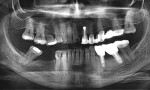

A sample case report from this study is presented in Figure 1 through Figure 13.